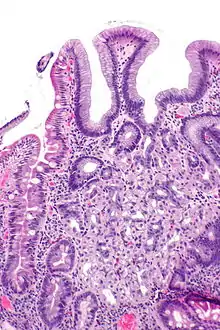

In medicine, heterotopia is the presence of a particular tissue type at a non-physiological site, but usually co-existing with original tissue in its correct anatomical location. In other words, it implies ectopic tissue, in addition to retention of the original tissue type.

In neuropathology, for example, gray matter heterotopia is the presence of gray matter within the cerebral white matter or ventricles. Heterotopia within the brain is often divided into three groups: subependymal heterotopia, focal cortical heterotopia and band heterotopia. Another example is a Meckel's diverticulum, which may contain heterotopic gastric or pancreatic tissue.